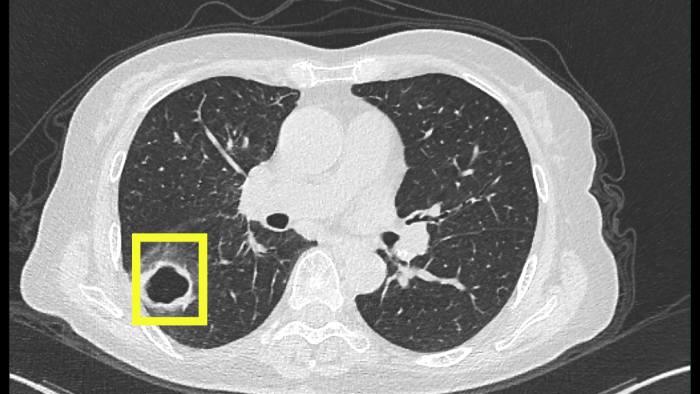

最開始以為只是普通感冒,但柴阿姨自行吃藥后并沒有好轉(zhuǎn)。感到焦慮的柴阿姨便到當(dāng)?shù)蒯t(yī)院就診,經(jīng)肺部CT檢查發(fā)現(xiàn),肺部出現(xiàn)空洞病灶。

當(dāng)?shù)蒯t(yī)院認(rèn)為有可能是肺結(jié)核,柴阿姨忐忑不安地來到衢州市人民醫(yī)院(溫州醫(yī)科大學(xué)附屬衢州醫(yī)院)感染科就診。

迷團(tuán)終于解開,原來引起柴阿姨肺部空洞的“罪魁禍?zhǔn)住辈皇欠谓Y(jié)核,而是真菌感染。

該患者是以咳嗽伴肺部空洞性病灶來就診的,最常見的病因是結(jié)核分枝桿菌引起的肺結(jié)核,但做了結(jié)核的相關(guān)檢查均未提示肺結(jié)核。而當(dāng)常規(guī)的檢驗(yàn)技術(shù)未發(fā)現(xiàn)病原菌時(shí),氣管鏡檢查及肺泡灌洗液的宏基因組測(cè)序就非常重要,可以讓患者少走很多彎路,使診斷及時(shí)明確,讓患者得到精準(zhǔn)治療。

尖端賽多孢菌感染常常累及呼吸道,可有咳嗽咳痰、發(fā)熱、咯血等癥狀。在肺部感染中,尖端賽多孢菌感染鑒別較為困難,且其感染的影像學(xué)與其他感染非常相似。當(dāng)普通抗感染效果不佳時(shí),要警惕真菌感染。